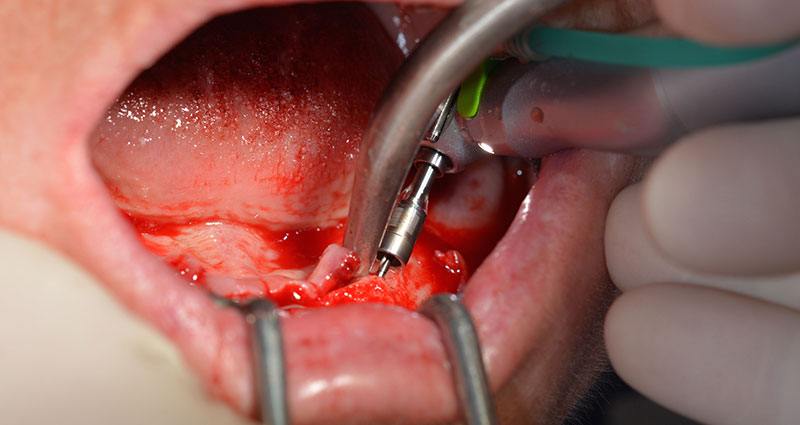

Nach der Entfernung der Unterkiefer-Restbezahnung erfolgte die krestale Schnittführung von Regio 37 bis Regio 47.

Zunächst wurde das Foramen mentale als limitierende anatomische Struktur dargestellt und die krestale Kortikalis mit dem geraden Handstück und einem großen Rosenbohrer geglättet (Abb. 4).